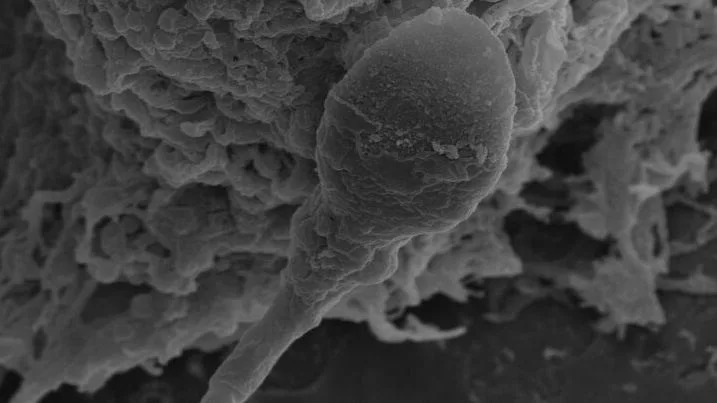

Can humans have babies in space? It may be harder than expected

When you buy through links on our articles, Future and its syndication partners may earn a commission. Humankind is bound to become a space-faring species, expanding beyond the bounds of Mother Earth, just as it, millions of years ago, spread out of its cradle in Africa. At least that's what space exploration leaders such as the world's richest man Elon Musk would like you to believe. However, there may be biological hurdles that could forever confine this vision to the realm of science fiction and human civilization to our Earthly soil. A new study found that sperm cells of mammalian species including humans, mice and pigs struggle to find their way through a female reproductive tract in microgravity to reach and fertilize an egg. Even when the sperm makes it to its destination, the study found that embryos formed in these conditions develop poorly compared to those evolving in normal gravity. The study, from researchers at the University of Adelaide in Australia, is just the latest addition to a growing pile of evidence that suggests mammalian reproduction in space might be quite complicated, if not impossible. There have been some previous studies with headlines stating mouse babies were born from stem cells subjected to months-long spaceflight, but most earlier research, conducted either in space or in microgravity simulators on Earth, has revealed a plethora of negative effects the space environment has on reproductive cells and embryos. "When you think about the future of space exploration and space settlements, it's happening. It's happening now," Nicole McPherson, a reproductive biologist at the University of Adelaide, Australia, and lead author of the paper, told Space.com. "I think people forget that for us to maintain these settlements without having to continually colonize them from Earth, we need to be able to reproduce in space." McPherson, whose previous work covered the effects of obesity and diet on the success of conception, got intrigued by the question of the possibility of in-space reproduction after watching a documentary hosted by British physicist Brian Cox. A discussion with her partner then spawned an idea for a unique research experiment. A chance encounter with the founder of space medicine company Firefly Biotech a week later allowed her to acquire a 3D clinostat for her lab. This device is a high-tech centrifuge that simulates microgravity by spinning vials with samples around two axes, effectively confusing the cells inside as to their position in space. In her experiment, McPherson and colleagues created a set-up holding human, mice and pig sperm cells in one part of the compartment and egg cells in the other, divided by a thin channel simulating the female reproductive tract. The researchers observed that 30% fewer sperms were able to make it to the egg compared to those in normal gravity. Scientists know sperm relies on a complex set of signals to find its way to an egg. Part of that navigation is driven by chemical cues, such as concentrations of the female hormone progesterone, but gravity seems to play a significant role too, McPherson said. "We know that sperm responds to chemical cues, but we also know that they like to swim near surfaces," she said. "Obviously, to know where surfaces are, you need to understand your position in time and for that you need gravity." The struggle of sperm to make it to the egg was only one part of the findings. When sperms managed to reach the eggs, the ensuing early-stage embryos, called blastocysts, initially appeared stronger than their counterparts conceived in gravity. However, when microgravity exposure continued, the superior quality of microgravity-conceived blastocysts deteriorated and the embryos started to lag behind their normal counterparts. McPherson thinks the initial quality gain observed in embryos formed after only four hours of microgravity exposure was due to the natural selection process that had occurred, allowing only the fittest sperms to reach the eggs. The subsequent deterioration in embryos that had been in microgravity for up to 24 hours was likely due to negative effects the absence of gravity has on the processes taking place in the quickly dividing embryonic cells. "There are so many changes that happen in those first 24 hours of embryo development," McPherson said. "You have the maternal and the paternal DNA coming together. You have lots of epigenetic remodeling that goes on to drive early foetal development. And that being exposed to zero gravity is actually really detrimental." McPherson said the researchers would, in the future, want to conduct similar experiments in reduced gravity, such as that of the moon or Mars, to see whether partial gravity might mitigate the problem. She thinks the findings have implications not just for the visions of space settlements, but also for commercial space tourism and babies potentially conceived on lunar and orbital honeymoons. The natural selection leading to the formation of stronger embryos after short microgravity exposures, on the other hand, could lead to advances in human IVF technologies that help treat infertility on Earth. In the future, the researchers would like to expose the embryos to longer microgravity spells to gain deeper insights into the processes taking place in space-like conditions. The study was published in the journal Communications Biology on Thursday (March 26).